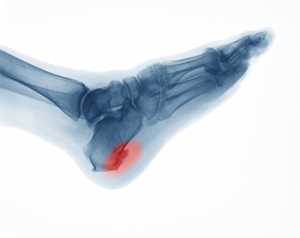

A heel spur is a growth of bone that forms from extra calcium deposits on the foot and that stretch from the heel bone to the foot arch. It is one of the most common causes of heel pain. Heel spurs are a quarter of an inch in length or smaller, though they may become larger in some cases. They cannot be seen from outside of the body but can become quite painful, especially when jumping, running, or walking. There may be swelling of the heel and ankle with heel spurs. Some of the primary causes of heel spurs are ill fitting or non-supportive footwear, wearing high heels, bruising under the heel bone, poor posture or other physical structural issues (such as flat feet or high arches), or being overweight or obese. Other possible causes are having a pre-existing medical condition, like diabetes or arthritis, over-training, repetitive hard impact or pressure on the heel, and aging with calcium leaving the bones and settling into the bloodstream and attaching to the surface of bones. Women are more prone to developing heel spurs than men because their hips are naturally wider in comparison to their knees which causes additional pressure to be placed on the heel with movement. Routine foot care and exercises to reduce ligament stress and relieve bone tension will help invigorate heel tissues, but sometimes surgery will be required to remove a heel spur. If you have a heel spur and it is causing pain and interfering with your functioning, consult with a podiatrist who can recommend the best course of treatment.

Heel spurs are formed by calcium deposits on the back of the foot where the heel is. This can also be caused by small fragments of bone breaking off one section of the foot, attaching onto the back of the foot. Heel spurs can also be bone growth on the back of the foot and may grow in the direction of the arch of the foot.

It is possible to have a heel spur without showing signs of any symptoms. However, if inflammation develops at the point of the spur’s formation, you may have pain while walking or running. In terms of diagnosis, sometimes all a doctor needs to know is that the patient is experiencing a sharp pain localized to the heel to diagnose a heel spur. Other times, an x-ray may be needed to confirm the presence of a heel spur.